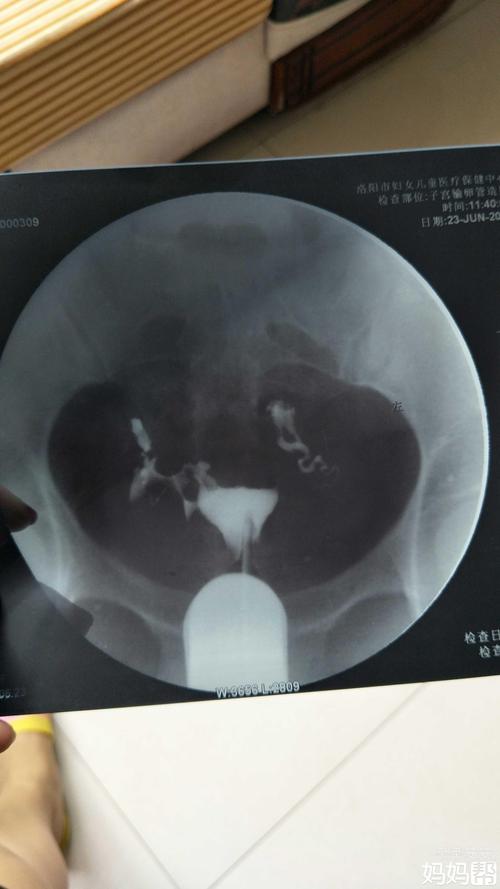

输卵管上举图片位置示意图

输卵管上举图片位置示意图,是很多婚后的女性朋友在发现自己的身体出问题后都会关注的方面问题。今天小编就收集到了几个名词供期网友们参照。